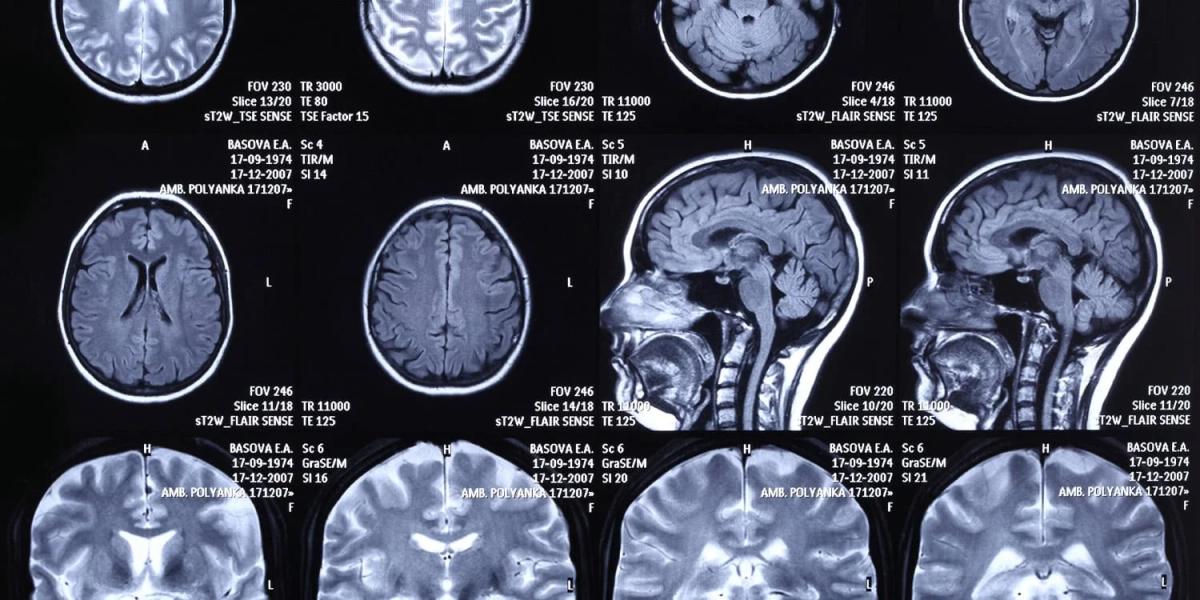

Brain Scans Reveal How Poor Sleep Fuels Negative Emotions in Alcohol Addiction

A new study in Drug and Alcohol Dependence examined 115 adults with alcohol use disorder (AUD) and found that poor sleep is strongly associated with heightened negative emotions, but not with craving or executive function. Functional MRI revealed that poor sleepers exhibited greater activity in the medial prefrontal and posterior cingulate cortices when viewing negative images, indicating heightened rumination. A second, independent sample of 102 AUD patients confirmed the link using a different insomnia questionnaire. Researchers suggest that treating sleep disturbances could mitigate emotional distress, a common trigger for relapse.